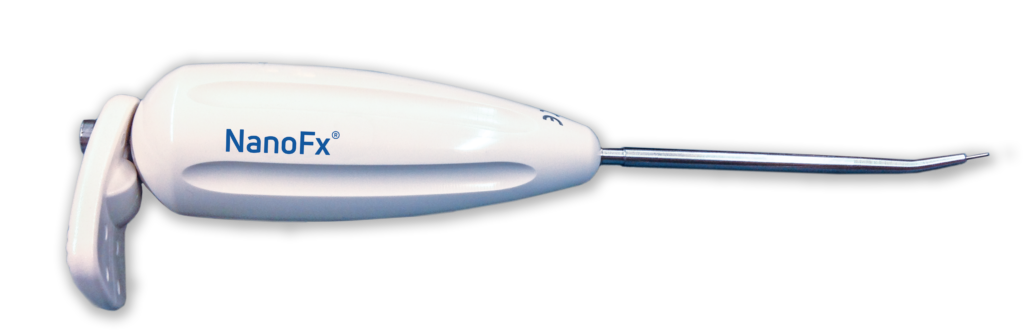

NanoFx® (Nanofracture®) is redefining standard microfracture procedures for the treatment of small, localized articular cartilage defects. Its 1mm diameter PleuriStik™ disrupts less surface area than a standard microfracture technique and was purposefully designed to reduce damage to the subchondral plate. Penetrating down to a 9 mm depth, NanoFx provides improved access to the targeted marrow cells, allowing for an enhanced healing environment three times deeper than standard microfracture awl techniques.

The smaller 1mm diameter of the NanoFx Pleuristik causes less trauma to the subchondral bone surface and may provide a greater perforation density compared to the much larger 2.5mm microfracture awl.3

Perforating down to 9mm versus a depth of 2mm improves access to the targeted marrow cells needed to initiate a healing response. Preclinical data demonstrates that the improvement in repair tissue quality and quantity was statistically significant due to deep versus shallow drilling.4

When tested against an awl or generic k-wire, NanoFx produced thin, fragmented cancellous bone channels without rotational heat generation. It achieved deeper bone perforation and a higher number of open trabecular channels, optimizing marrow access and minimizing bone trauma.6

Drill-free bone perforations optimize trabecular bone venting and avoid channel closure from K-wire drilling caused by bone deposits that clog the trabecular tributaries. Studies have shown that deeper marrow access leads to an improved biological response and better tissue quality.4, 10

The sharp disposable needle tip provides better control during placement of the perforations and avoids slippage and damage to surrounding tissues.